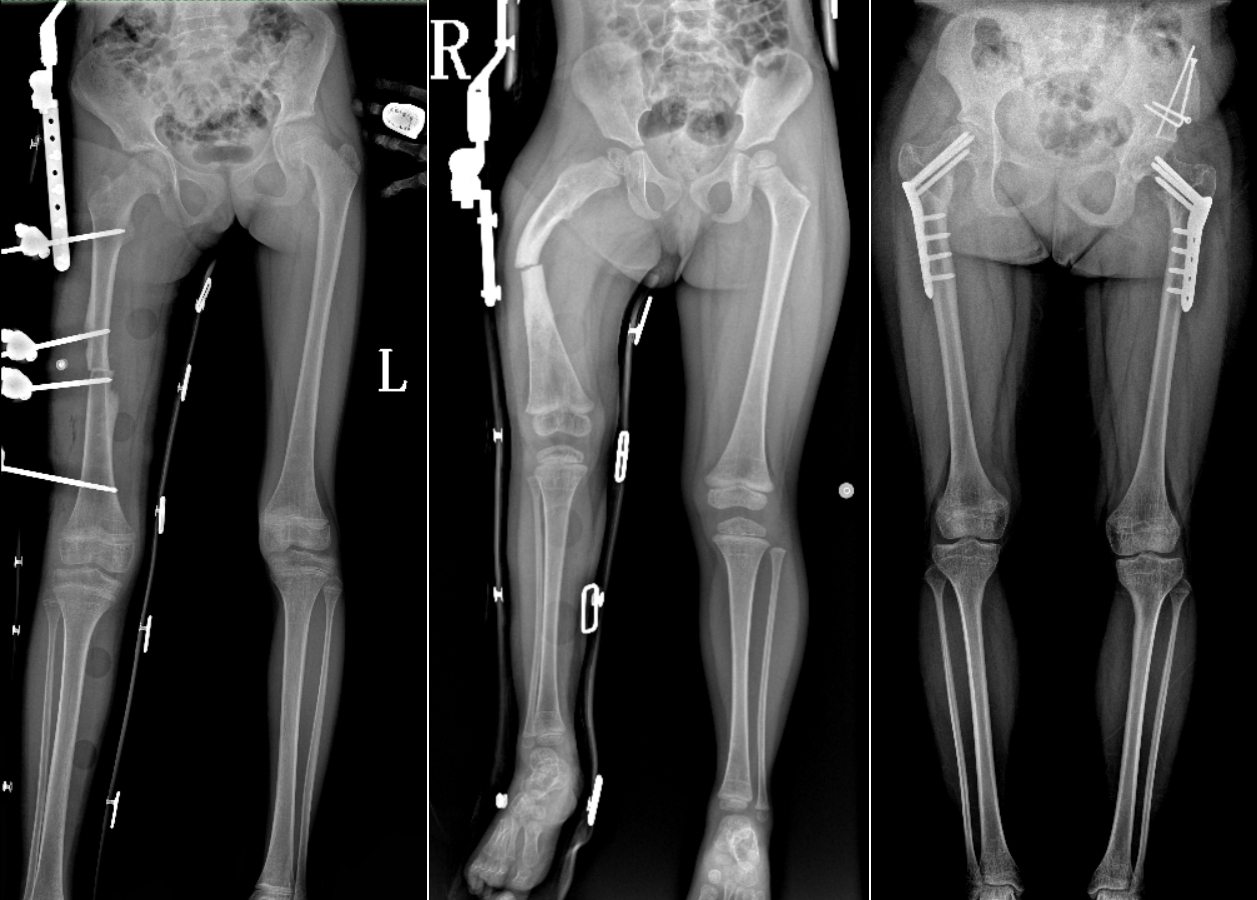

PLX8600 dynamic flat panel DR independently developed by Perlove Medical adopts an effective field of view of 17"*34", which can get the image of the whole spine or the whole lower limb in one exposure. Compared with the DR equipment of multiple photography and then software splicing, PLX8600 solves the problems of uneven density of spliced images, image alignment and magnification effect at the splicing place, and brings a real large field of view image solution to the clinic.